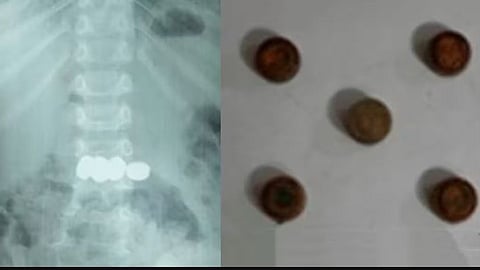

അഞ്ച് വയസുകാരന് അഞ്ച് ബാറ്ററികള് വിഴുങ്ങി, മണിക്കൂറുകള് നീണ്ട ശസ്ത്രക്രിയയില് പുറത്തെടുത്തു

മേപ്പാടി: രണ്ടു വയസ്സുകാരന് വിഴുങ്ങിയ അഞ്ച് കോയിന് ടൈപ്പ് ബാറ്ററികള് എന്ഡോസ്കോപ്പിയിലൂടെ വിജയകരമായി പുറത്തെടുത്തു. ബത്തേരി മൂലങ്കാവ് സ്വദേശികളുടെ മകനാണ് കളിപ്പാട്ടത്തിലുണ്ടായിരുന്ന ബാറ്ററികള് വിഴുങ്ങിയത്.

കുട്ടി ബാറ്ററികള് വിഴുങ്ങുന്നത് കണ്ടതോടെ വീട്ടുകാര് ആശുപത്രിയില് എത്തിക്കുകയായിരുന്നു. എന്ഡോസ്കോപ്പിയിലൂടെയാണ് ബാറ്ററികള് പുറത്തെടുത്തത്. ഡോ.മൂപ്പന്സ് മെഡിക്കല് കോളജിലെ ഗാസ്ട്രോ എന്ററോളജി വിഭാഗം സ്പെഷലിസ്റ്റ് ഡോ.സൂര്യനാരായണയുടെ നേതൃത്വത്തിലായിരുന്നു ബാറ്ററികള് പുറത്തെടുത്തത്. സമയബന്ധിതമായി ചികിത്സ ഉറപ്പാക്കാനായതിനാലാണ് വലിയ അപകടം ഒഴിവാക്കാന് സാധിച്ചതെന്നും കുട്ടിയുടെ ആരോഗ്യനില തൃപ്തികരമാണെന്നും ആശുപത്രി അധികൃതര് അറിയിച്ചു.

ബാറ്ററികള് ആമാശയത്തില് എത്തിയാല് ഉള്ളിലെ അസിഡിക് പ്രവര്ത്തനത്തിലൂടെ പൊട്ടാനുള്ള സാധ്യതയുണ്ടെന്നും അങ്ങനെയുണ്ടായാാല് കുടല്, കരള് തുടങ്ങിയ അവയവങ്ങളില് ഗുരുതരമായ ക്ഷതം ഉണ്ടാകുമെന്നും ഡോക്ടര്മാര് പറഞ്ഞു. ഇത്തരത്തില് കളിപ്പാട്ടങ്ങളുമായി ഇരിക്കുന്ന കുട്ടികള് മുതിര്ന്നവരുടെ നിരീക്ഷണത്തില് ആയിരിക്കണമെന്ന് ഡോക്ടര്മാര് പറഞ്ഞു. ഡോ.അഖില്, ഡോ. അഞ്ജന എന്നിവരും ചികിത്സയില് പിന്തുണ നല്കി.